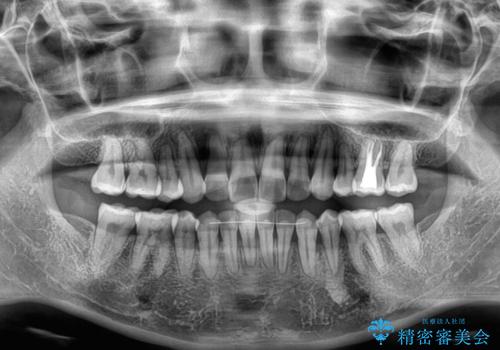

舌の突出癖が原因で後戻りをしたため、舌のトレーニングをしっかりと行っていただき、口元の突出感を改善することができました。

インビザラインの装着時間が守れず、1年強で終わる予定でしたが、4年間を要することとなりました。